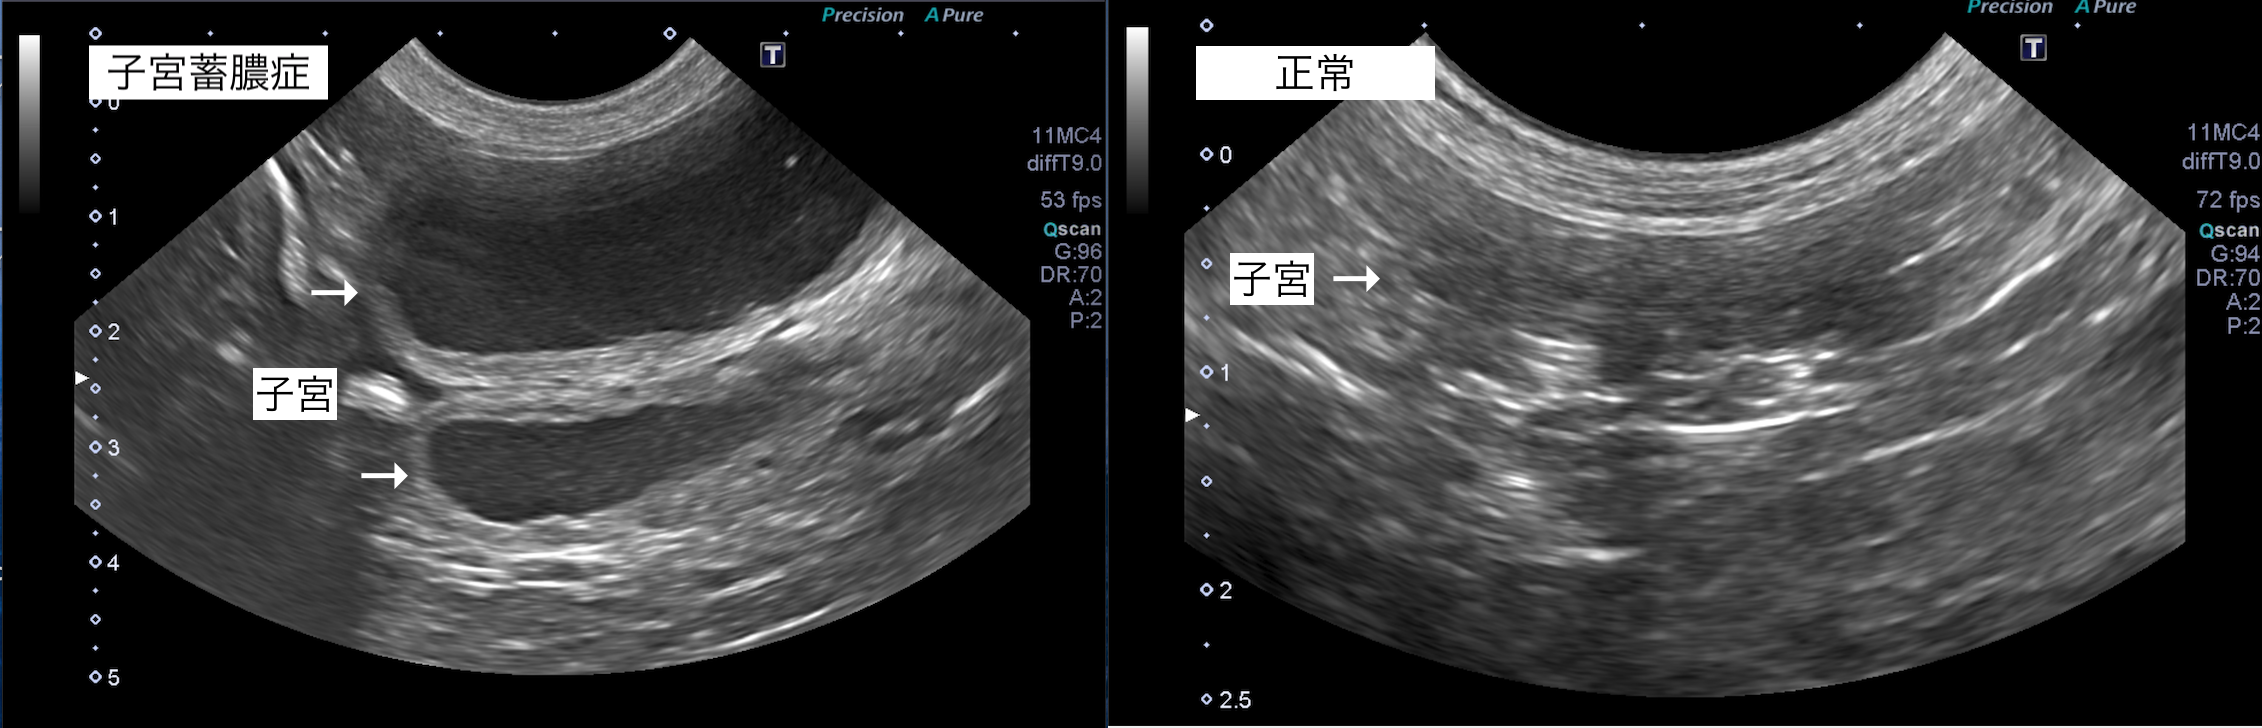

子宮蓄膿症の犬の1例(避妊・去勢手術)

子宮蓄膿症は、避妊手術を行っていない犬猫に起こり、子宮腔内に膿が溜まってしまう病気です。

超音波検査では子宮に液体貯留が認められたため、子宮蓄膿症と診断しました。